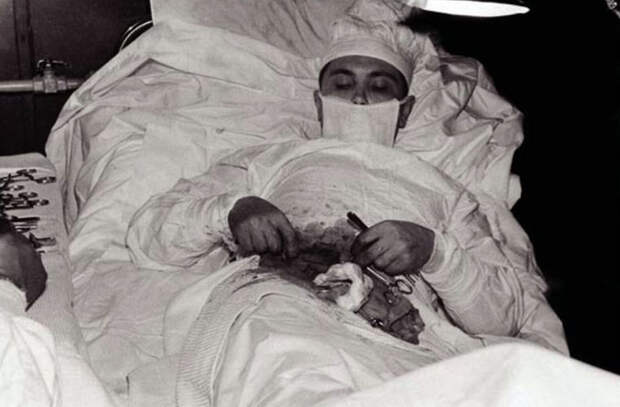

Рогозов оперирует самого себя в ходе полярной экспедиции

1 час 45 минут потребовалось Леониду Рогозову, чтобы удалить себе аппендикс

Случается также, что жизнь ставит человека в условия, когда рискованный эксперимент над собой оказывается вынужденной необходимостью. В 1961 году советский хирург Леонид Рогозов, будучи врачом в составе 6-й Антарктической экспедиции, диагностировал у себя аппендицит. Учитывая погодные условия, препятствующие эвакуации, и безрезультатно перепробовав различные методы лечения (голодание, местный холод, прием антибиотиков), Рогозов принимает волевое решение прооперировать самого себя.

Леонид Рогозов после операции, которую проводил сам себе

Разместившись на койке с наклоном на левый бок, Рогозов произвел обезболивание раствором новокаина и сделал надрез. Так началась операция, вошедшая во все отечественные учебники по медицине. Для помощи в проведении этого исключительного хирургического вмешательства из участников экспедиции было выбрано два ассистента, один из которых подавал инструменты, а второй — держал зеркало у живота Рогозова для обзора и направлял свет лампы, так как видеть рану, Рогозов, разумеется, не мог. Зеркало помогало частично, местами приходилось действовать наощупь. Так, без перчаток, больной удалил сам у себя злосчастный аппендикс. Совершенно обессиленный, через 1 час 45 минут он закончил операцию, которая, к счастью для всех, прошла успешно.